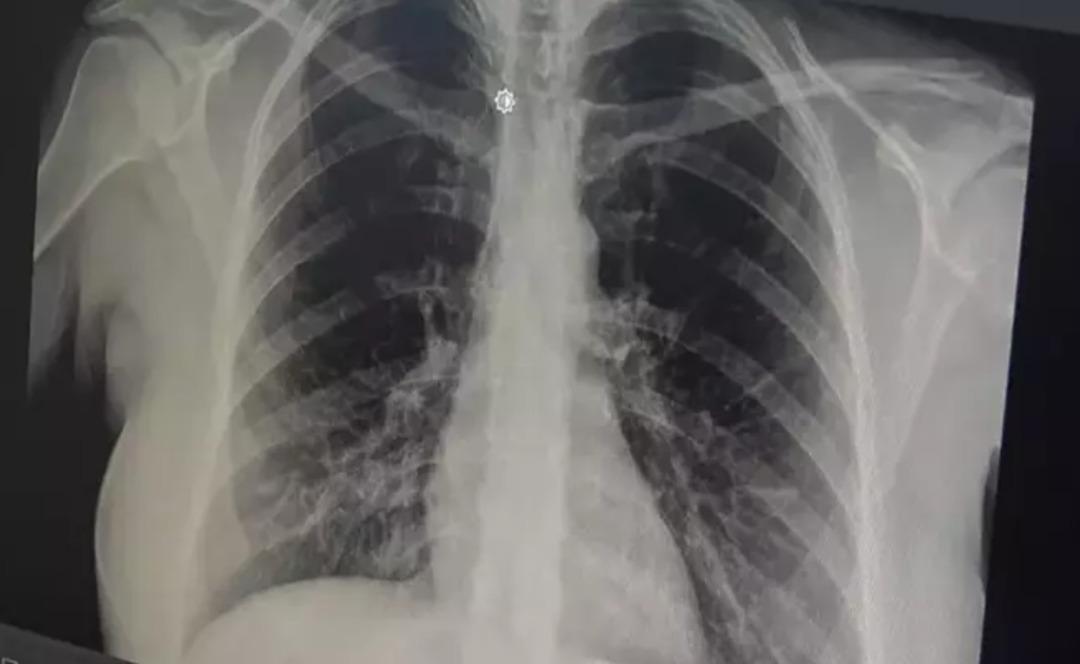

Göğüs Hastalıkları Uzmanı Prof. Dr. Tevfik Özlü, akut bronşitin giderek yayıldığına dikkat çekerek önerilerde bulundu. prof. Akut bronşitin ilk belirtilerinin boğaz ağrısı, hafif ateş ve burun akıntısı olduğunu ancak enfeksiyon bronşlara yayıldığında göğüs ağrısı ve şiddetli öksürüğün ortaya çıktığını söyleyen Dr. Özlü, akut bronşitin hafif ve tedavi edilebilir bir hastalık olduğunu belirterek, hastaların doktora başvurması konusunda uyardı.

prof. Akut bronşitin solunum yolu virüslerinin neden olduğu bir hastalık olduğunu belirten Dr. Özlü, şöyle konuştu: “Günümüzde çok sık gördüğümüz bir hastalık. Genelde hastalar şöyle tarif ediyor: 'Öncelikle boğazım ağrıyordu, boğazım ağrıyordu. hafif ateş, burun akıntısı, hapşırma, geniz akıntısı ve öksürük “2-3 gündür göğsümdeydi. Nefes alırken acı hissediyorum. Göğsünde bir çalı varmış gibi geliyor ve. Nefes aldığımda oraya sıkışıp kalıyor.” Enfeksiyonun göğse kadar indiğini iddia ediyorlar. Bu doğrudur çünkü akut bronşit, solunum yolu virüslerinin neden olduğu bulaşıcı bir hastalıktır. Bu enfeksiyon üst solunum yollarıyla sınırlı olmayıp aynı zamanda alt solunum yollarımız ve bronşlarımız.

Akut bronşitin en önemli belirtisinin öksürük olduğunu vurgulayan Prof. Dr. Tevfik Özlü, “Kuru öksürük veya balgamlı öksürük şeklinde kendini gösterebiliyor. Bazen belirti daha çok hırıltılı solunum ve nefes darlığı şeklinde hissedilebiliyor. Yüksek ateş genellikle herhangi bir rahatsızlığa neden olmaz ancak bazen bakteriyel enfeksiyonlar da ortaya çıkabilir” dedi.

Bronşitin genel olarak hafif seyreden bir hastalık olduğunu ancak belirtilerin artması durumunda mutlaka doktora başvurulması gerektiğini belirten Özlü, şöyle konuştu: “Altta yatan kronik bir hastalık, astım veya kronik obstrüktif KOAH gibi bir akciğer hastalığı varsa, bronşitin akut alevlenmesidir. kronik hastalık eşlik edebilir ve genel akut bronşit, nefes darlığı, hırıltılı solunum, yorgunluk, yüksek ateş gibi ağır belirtilerle ortaya çıkabilir. semptomların alevlenmesi varsa, o zaman bir doktora danışmak gerekir. Genel olarak hafif ve tedavi edilebilir bir hastalık olduğunu söylemek isterim” dedi.